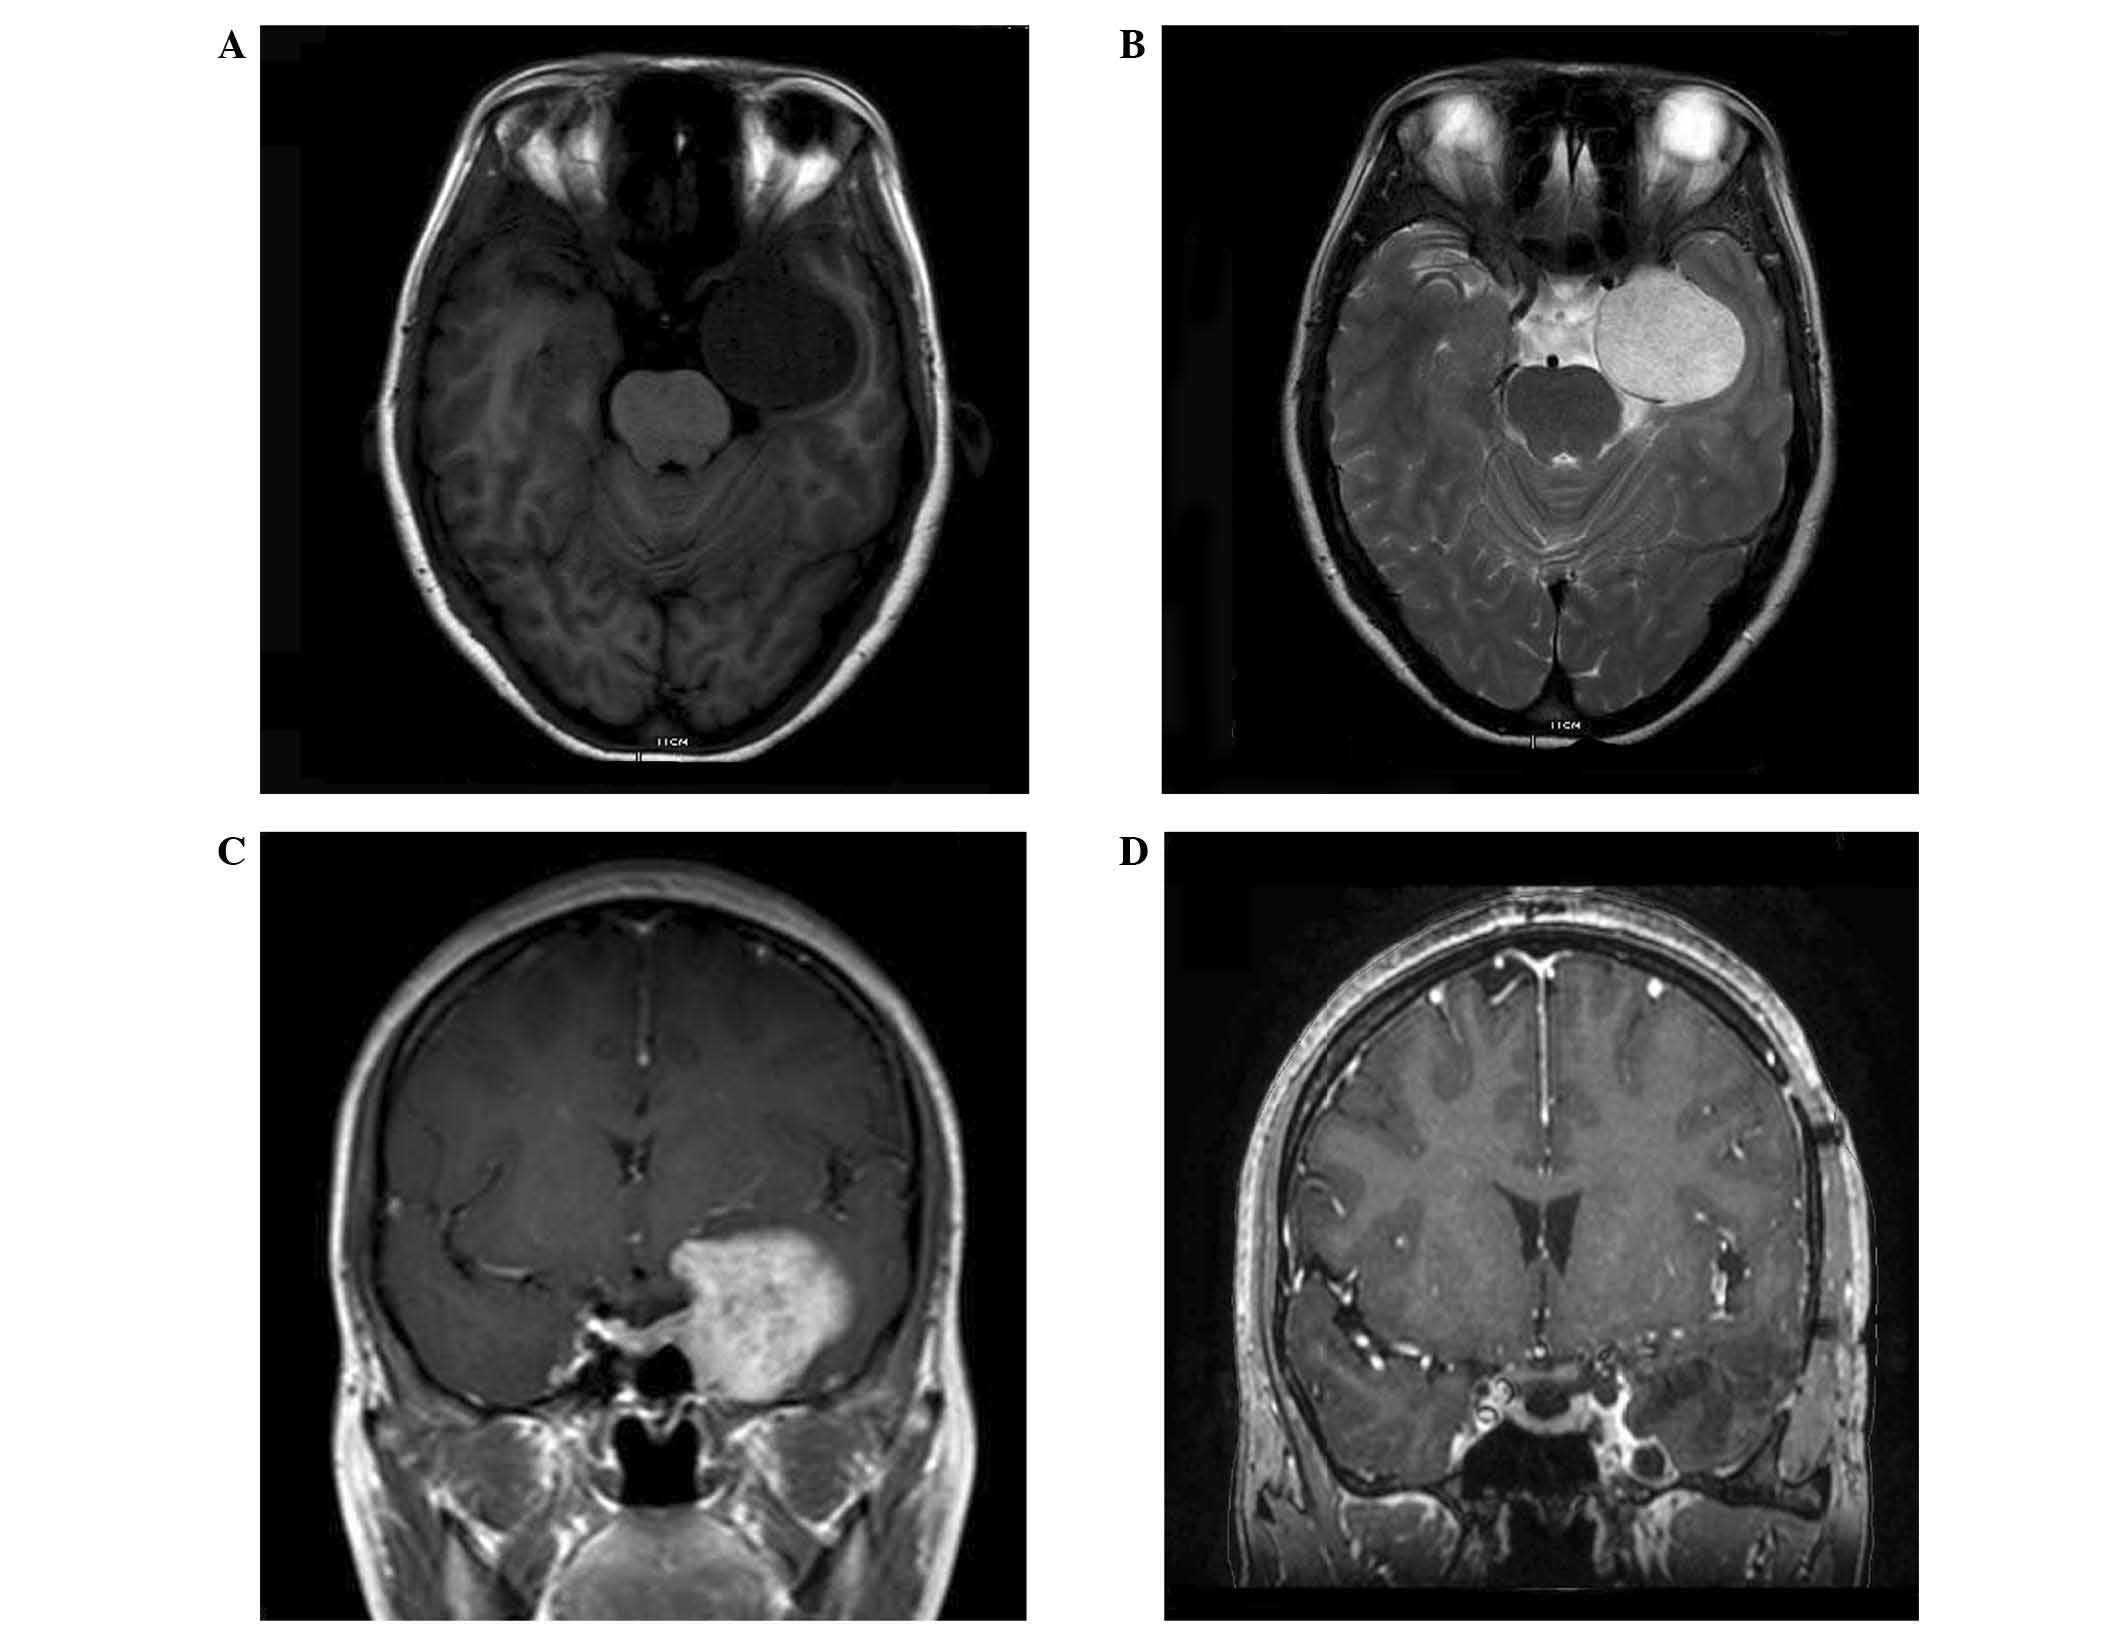

Radiologically, an iso or low signal intensity on T1-weighted MRI, and a bright, high signal intensity on T2-weighted MRI was observed in all patients. All tumors exhibited strong enhancement following administration of the contrast medium gadolinium-diethylene triamine pentaacetic acid (Fig. 1A–C).

Figure 1.

MRI revealed a cavernous sinus hemangioma on the left side. (A) Axial T1-weighted imaging showed a low-signal intensity lesion; (B) T2 weighting revealed a high signal intensity lesion; (C) Coronal T1-weighted contrast-enhanced imaging revealed strong enhancement and a pre-treatment tumor volume of 33.2 cm3, and (D) at 40 months after treatment, the tumor volume shrank to 2.5 cm3.

Tumor control was achieved in all patients during the follow-up period. Remarkable shrinkage was achieved in 6 patients and minimal shrinkage was achieved in 1 patient. The patient with minimal shrinkage was observed during the 6 months follow-up, and the volume was reduced from 10.5 cm3 to 5.9 cm3 (reduced 44%). In another patient with 40 months of follow-up, the tumor volume reduced from 33.2 cm3 to 2.5 cm3, only 7.5% of the initial volume. No patients experienced tumor progression prior to the date of last follow-up.

The marginal doses delivered to the lesions require the thorough consideration of radiation injury of the critical structures around the cavernous sinus, including the optic apparatus. Nakamura et al (14) suggested that the treatment of CSHs necessitated lower radiosurgical doses compared with those required for other benign tumors. Yamamoto et al (6) analyzed dose-treatment responses in 38 reported cases of CSH treated with radiosurgery, suggesting that a peripheral dose of 14–15 Gy was sufficient for controlling CSH growth, and that 10–12 Gy was the threshold dose for the control of tumor growth. In the current study, 1 patient who was diagnosed by biopsy had a tumor volume of 33.2 cm3 and was treated with a low marginal dose (10 Gy). The tumor volume was subsequently reduced to only 7.5% of the initial volume, which indicated that CSH were highly radiosensitive. The ipsilateral abducens nerve palsy was observed to be in a state of partial remission during the 40 months of follow-up (Fig. 1D).